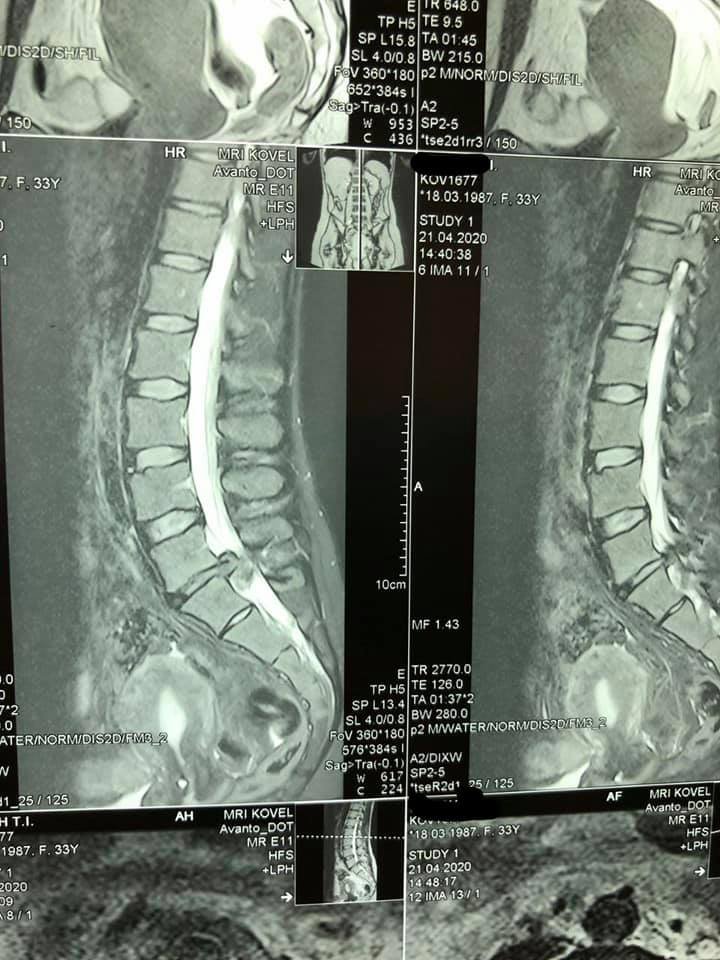

Медики негайно провели МРТ та встановили причину погіршення стану здоров'я - секвестровану грижу L5-S1 з критичним стенозом спинномозкового каналу.

Лікарі пояснили, що грижовий мішок створював тиск на структури, близькі до спинного мозку.